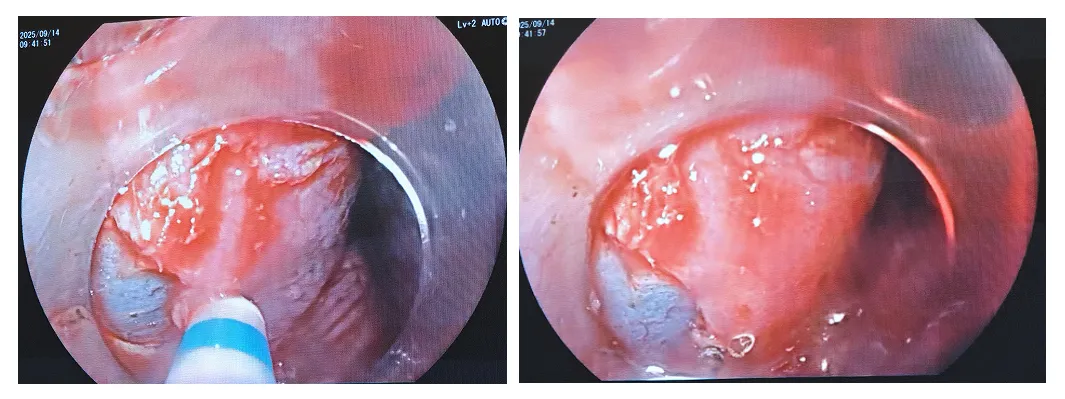

9:15开始,病灶在27-32cm环3/4周,操作前一天做过碘染,明确边界,对现在观察边界有点影响,不够清晰。3/4周病灶,有可能要做环周切除,术后狭窄率达80-100%会有狭窄。现在与患者家属商量是否推迟做这台ESD术。9:28与患方沟通后,家属要求继续手术,现在标记。

9:38此例选用的是富士3.8mm通道的治疗镜,外径10.5mm,吸引及进出器械好,因镜子粗一些,所以操作灵敏度比细镜会差一点;爱尔博电刀,胃、食管、肠道ESD的电切参数都是3-2-4,电凝是强凝模式2-50W选用的是Dual刀,粘膜下注射的是生理盐水加地塞米松,预防术后狭窄,1mg DXM配1ml NS。个人习惯透明帽伸出3mm左右总体策略尽量保留1/4正常粘膜基础上,尽量完整剥离病灶沿标记点旁粘膜下注射水垫隆起后,先是从1/4正常粘膜边界做切开,然后在肛侧做环形切开再从上向下切开,利用重力因素剥离9:40-45,现在沿肛侧标记点,做切开,再剥离。遇到出血,先止血

9:52现在转到口侧做环形切开粘膜层,因为有心脏搏动,食管收缩,加上镜子粗一些,所以操作空间比较小。